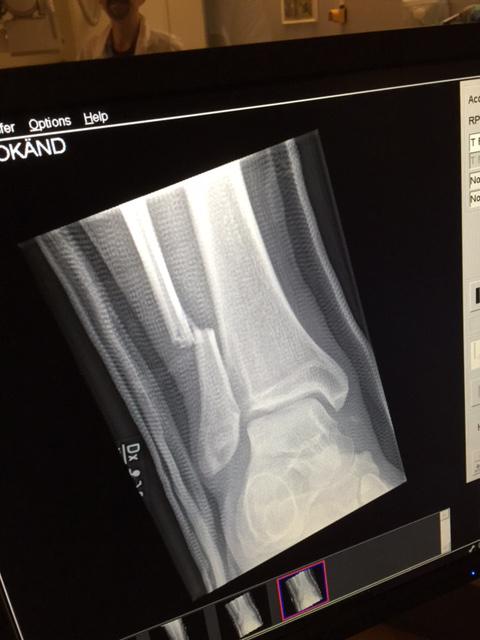

Dave Grohl just broke his leg, falling off stage in Sweden, and kept rocking shortly after like a boss. pic.twitter.com/7d1u5kKQC7

Durante la presentación de la canción “Monkey Wrench”, Grohl se cayó del escenario, y se quedó en el piso por varios minutos, antes de ser llevado tras bambalinas.

“Oigan, damas y caballeros. Los amo, pero creo que me acabo de romper la pierna”, anunció Grohl desde el piso.

Eventualmente, Grohl regresó al escenario con la pierna envuelta y asegurada, y terminó el concierto sentado en una silla.